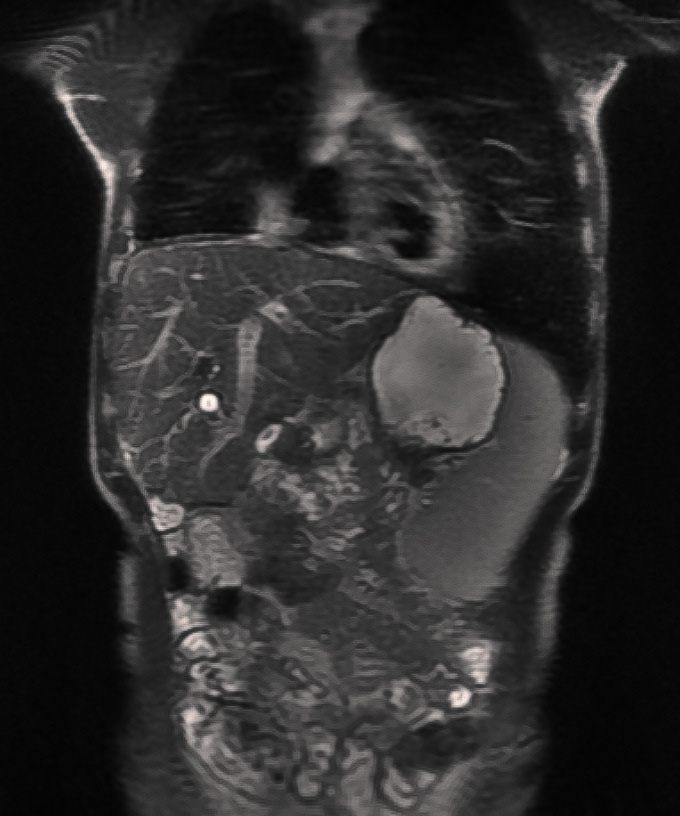

MRI scan of Silas in March 2019. On the left, the metal stent inserted into Silas’s fourth and current liver is visible. The stent holds the bile duct open from the inside, allowing bile to flow normally into the intestine.